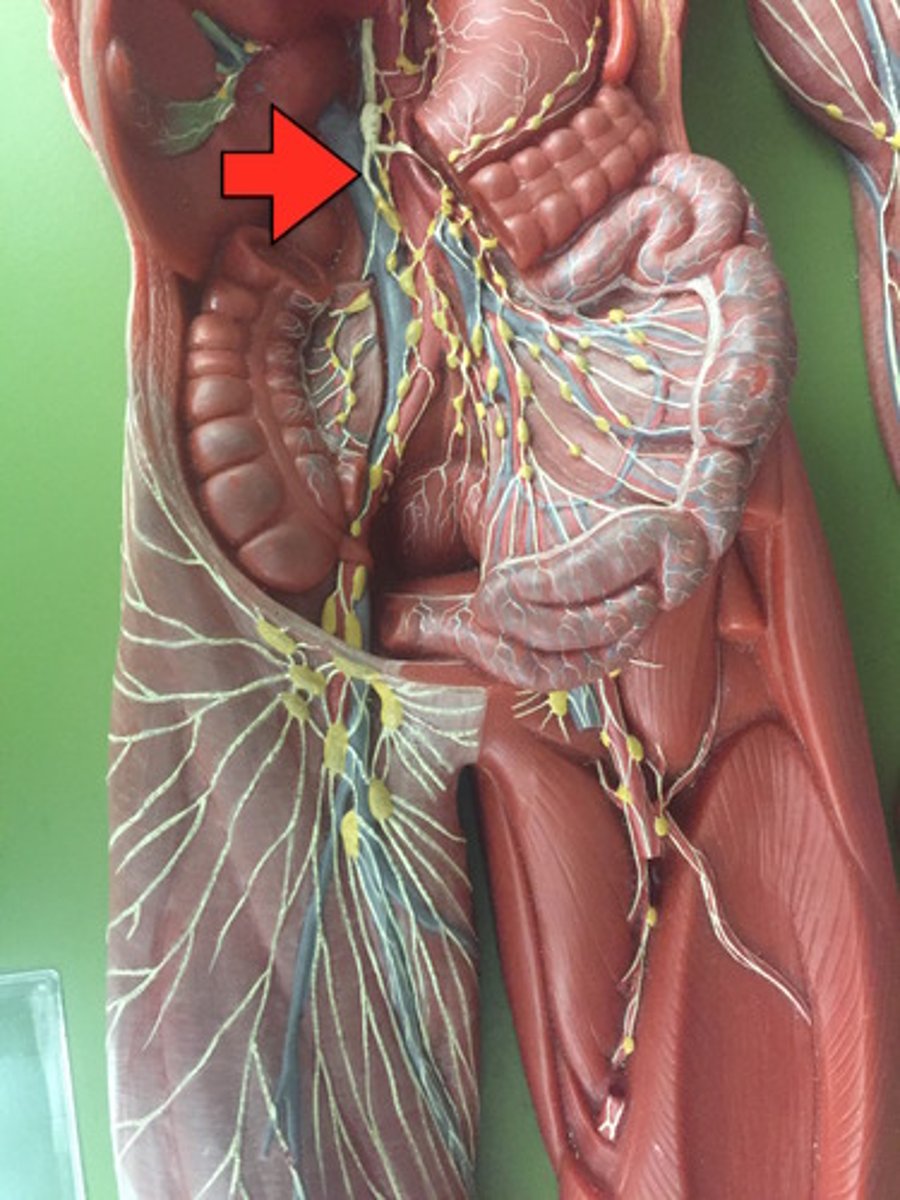

Superior mesenteric artery

Inferior mesenteric artery